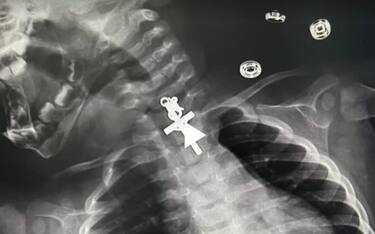

Perù, bimba ingoia un crocifisso: salvata da intervento chirurgico Mondo La bambina quando è arrivata in ospedale piangeva e respirava male. Una radiografia ha rivelato... 15 nov - 11:09